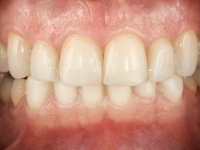

Após análise clínica e imagiológica foi proposto ao paciente recuperar a dimensão vertical da oclusão essencialmente à custa de incrementos oclusais inferiores utilizando “overlays” no sector posterior e facetas no sector anterior. A coroa aparafusada sobre o implante 3.5 seria substituída, no sentido de acompanhar este incremento. Na maxila o dente 2.6 teria extração indicada e posteriormente seria reabilitado com um implante e respetiva coroa. No sentido de reabilitar esteticamente o paciente duma forma minimamente invasiva, foi proposta a colocação de facetas feldespáticas no sector antero-superior. O objetivo de aumentar ligeiramente a D.V.O., teria como função “proteger” eficazmente o sector antero-superior.

Realizado o diagnóstico e tomada a decisão quanto ao tratamento a executar, tornou-se importante definir qual a sequência de trabalho a adotar no sentido de conseguir a reabilitação da D.V.O. (V.D.O), de forma progressiva e equilibrada. Na primeira fase fez-se uma pré-impressão da arcada inferior com silicone tipo “putty” e em seguida realizou-se o preparo dentário de todo o sector posterior. O preparo para os overlays foi feito coronalmente à linha amelo cementaria no sentido de ser o mais conservador possível. A impressão foi feita com técnica de dupla mistura após afastamento gengival realizado com pasta de caulino. A provisória foi realizada com resina composta de polimerização dual. Em laboratório foram realizados os overlays após se ter aberto ligeiramente (1,5mm) a D.V.O. nos modelos montados em articulador semi-ajustável. Simultaneamente o sector antero-inferior foi encerado no sentido de acompanhar este aumento da D.V.O. Também foi confecionada uma chave de silicone translucido para posterior confeção dos provisórios antero-inferiores. Em boca foi primeiro realizada a provisionalização dos dentes anteriores utilizando resina composta previamente aquecida após preparação das superfícies dentárias para a adesão. Foi colocado o dique de borracha para promover o isolamento absoluto e posteriormente foram colados os overlays. Em laboratório foi realizada nova chave de silicone para confecionar os provisórios antero-superiores. Seguidamente em boca foram preparados os seis dentes antero-superiores após colocação do fio de afastamento gengival. Feita a preparação adequada das superfícies dentárias foi realizada a impressão com técnica de dupla mistura e a respetiva provisória. Em laboratório foram confecionadas 6 facetas feldespáticas num modelo de trabalho tipo “Geller”. A provisória foi removida e as facetas foram coladas em boca utilizando um isolamento relativo competente. Esta opção foi tomada em virtude de uma prévia experiencia negativa com a colocação do dique de borracha na mandibula. Após a colagem dos laminados antero-superiores foram dadas 12 semanas para avaliar a adaptação do paciente à nova situação e então iniciar a confeção das facetas antero-inferiores. Após colocação do fio de afastamento gengival. foram feitos os preparos dentários adequados e em seguida foi feita a impressão. Também foi feita a preparação do dente 3.4 que, entretanto, tinha sofrido uma fratura do overlay. As facetas e a restauração do 3.4 foram realizadas num modelo de trabalho tipo “Geller”. Após remoção da provisória, as facetas foram coladas em boca, utilizando um isolamento relativo pelas razões apontadas anteriormente. Após colocação do trabalho o paciente foi reabilitado por outros colegas com um implante na zona do 2.6 e substituição da coroa aparafusada sobre o implante colocado no local do 3.5. Posteriormente surgiram fraturas nos overlays dos dentes 4.7 e 3.7 que foram reabilitados com overlays em Zr.